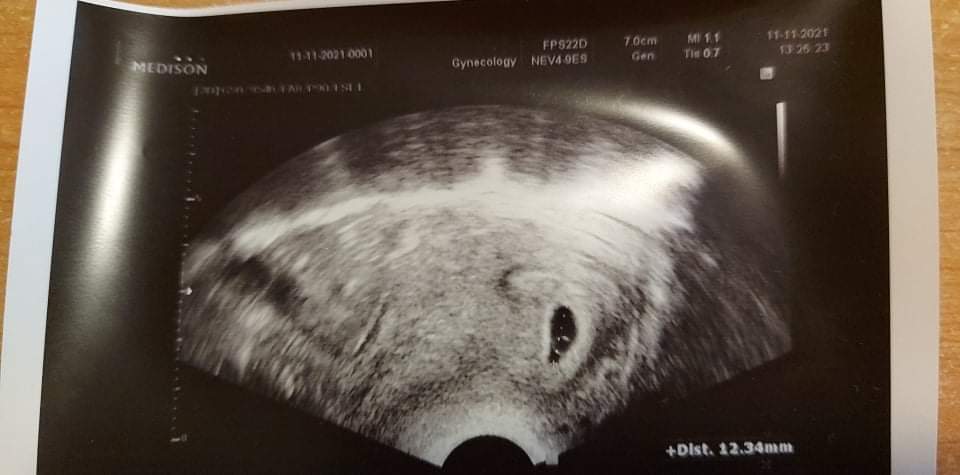

@fialka444 přidávám foto z 5+5🍀